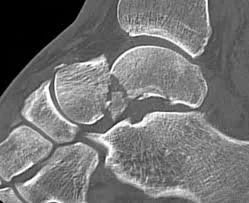

Talus fractures may involve different regions of the bone, including the talus neck, body, head, or lateral process, each with distinct injury patterns and treatment considerations. Even fractures that appear minimally displaced on initial imaging can have significant implications due to the importance of precise joint alignment and blood flow.

Imaging is essential for accurate diagnosis. X-rays are used initially, but CT scans are frequently obtained to define fracture patterns, displacement, and joint involvement. MRI may be considered in select cases to assess cartilage injury or blood supply to the talus.